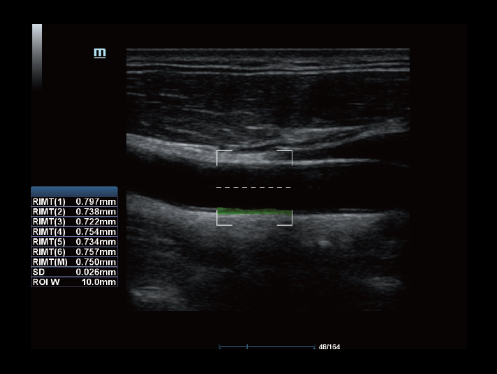

Echo Boost yang canggih

Terobosan beruntun Mindray untuk visualisasi gambar ultrasound terbaik.